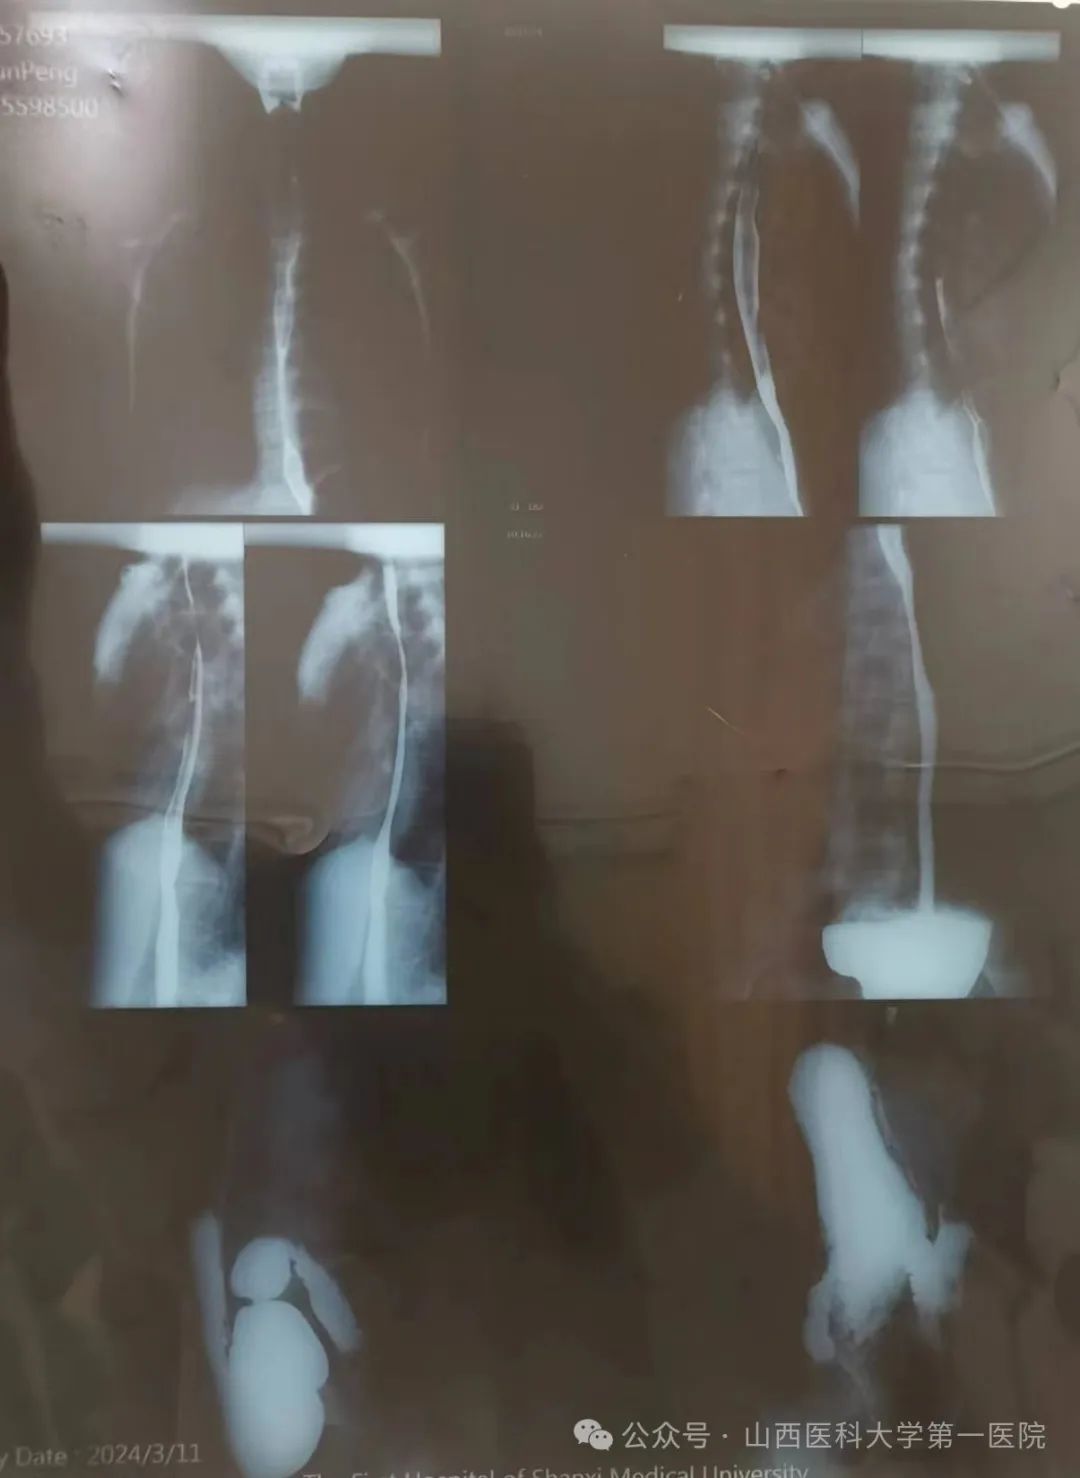

临床营养科接诊一名重度营养不良年轻患者,该患者近两年来无明显诱因反复出现进食后腹胀、腹痛、恶心、纳差,症状进行性加重,进食量逐日减少,检查提示胃下垂及十二指肠淤滞,其带来的进食障碍使体重严重不足,BMI仅12.6kg/m2,肌肉量减少,脂肪流失,合并贫血及闭经,身体的不适导致无法正常生活学习。

十二指肠淤滞是由于各种原因引起的十二指肠阻塞,以致十二指肠阻塞部位的近端扩张、食糜壅积而产生的临床综合征,常表现为间歇性进食后腹胀、腹痛、嗳气、恶心、呕吐等。多发生于瘦长体型的中、青年女性,常见病因包括:肠系膜上动脉过长、过短;肠系膜上动脉变异,从腹主动脉分出的部位过低或分出时角度狭窄;异常粗大的静脉横压在十二指肠前方;脊柱前凸畸形使十二指肠占有的空隙减少;瘦长型或内脏下垂者肠管重量牵引肠系膜根部。患者食物摄入不足、体重下降会导致中、重度营养不良的发生,治疗原则需进食无渣食物、少量多餐,餐后采取俯卧位或左侧卧位;如患者进食量加口服肠内营养制剂达不到目标能量的60%,需要置入鼻空肠管,持续滴入营养液,改善营养状况,同时给予消化酶、胃肠动力药等;长期保守治疗无效,影响营养状况或正常工作时,可行手术治疗。